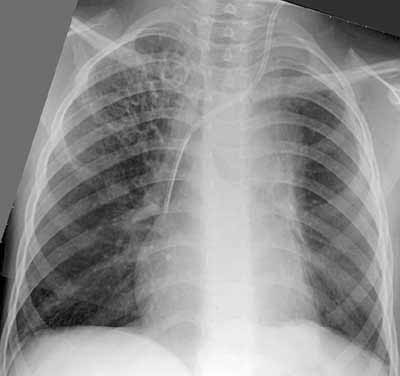

Муковисцидоз.

Рис. 2. Положительная динамика после интенсивного консервативного лечения.